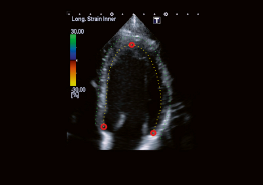

Wall Motion Tracking (WMT) позволяет зафиксировать и проанализировать движение стенок миокарда. WMT отслеживает деформацию миокарда и смещение его участков (спекл-трекинг). Технология может быть использована как в 2D, так и в 3D режимах. Спеклы - это изменения ультразвука отражателями в ультразвуковом пучкеnd ™..Toshiba делает акцент на большой роли стандартизации параметров деформации миокарда и активно поддерживает Объединенную рабочую группу Американского общества эхокардиографии (ASE) и Европейской ассоциации Эхокардиографии (EAE). Анализ WMT может выполняться как в онлайн, так и в автономном режиме на основе файлов DICOM, содержащих необработанные клипы с данными, отправленные на рабочую станцию. WMT незаменим для диагностики ишемических повреждений миокарда и определения точной локализации инфаркта.

Технология 2D Wall Motion Tracking - проводит сегментарный анализ (16 или 17 сегментов по ASE) миокарда для вычисления циркулярной, радиальной и продольной деформации;

Для определения начального контура полости левого желудочка необходимо выбрать три точки в конце диастолы.